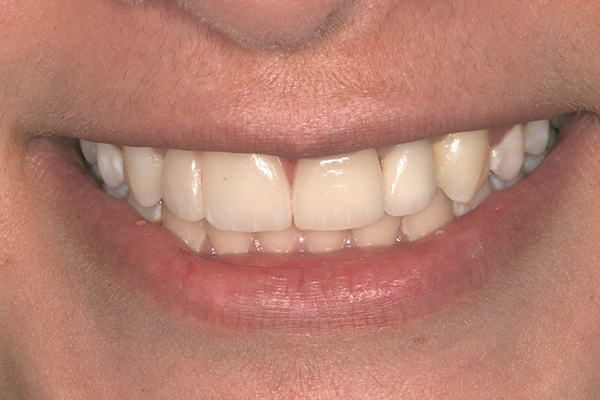

Fig 13 to Fig 16. Post-treatment photographs.

When the patient was 19 years old, the lithium-disilicate veneers and the ceramic crown were tried in and evaluated. Following modification, the veneers were carefully cemented with an adhesive resin cement following application of silane to the intaglio surfaces, etch of the enamel, and application of primer and adhesive. The intaglio surface of the implant crown was treated with a porcelain etch product and silane, and the crown was cemented with carboxylate luting cement with 1 drop of water for retrievability. A paintbrush was used to apply a thin layer of cement to minimize excess. Any excess cement on the veneers and crown was meticulously removed, and the margins and occlusion were carefully checked. The patient returned 2 weeks later (Figure 13 through Figure 18) for a review of her oral hygiene and for fabrication of a nightguard. The patient was happy with the esthetic result and exclaimed she had been stopped on the street and told she had a beautiful smile.